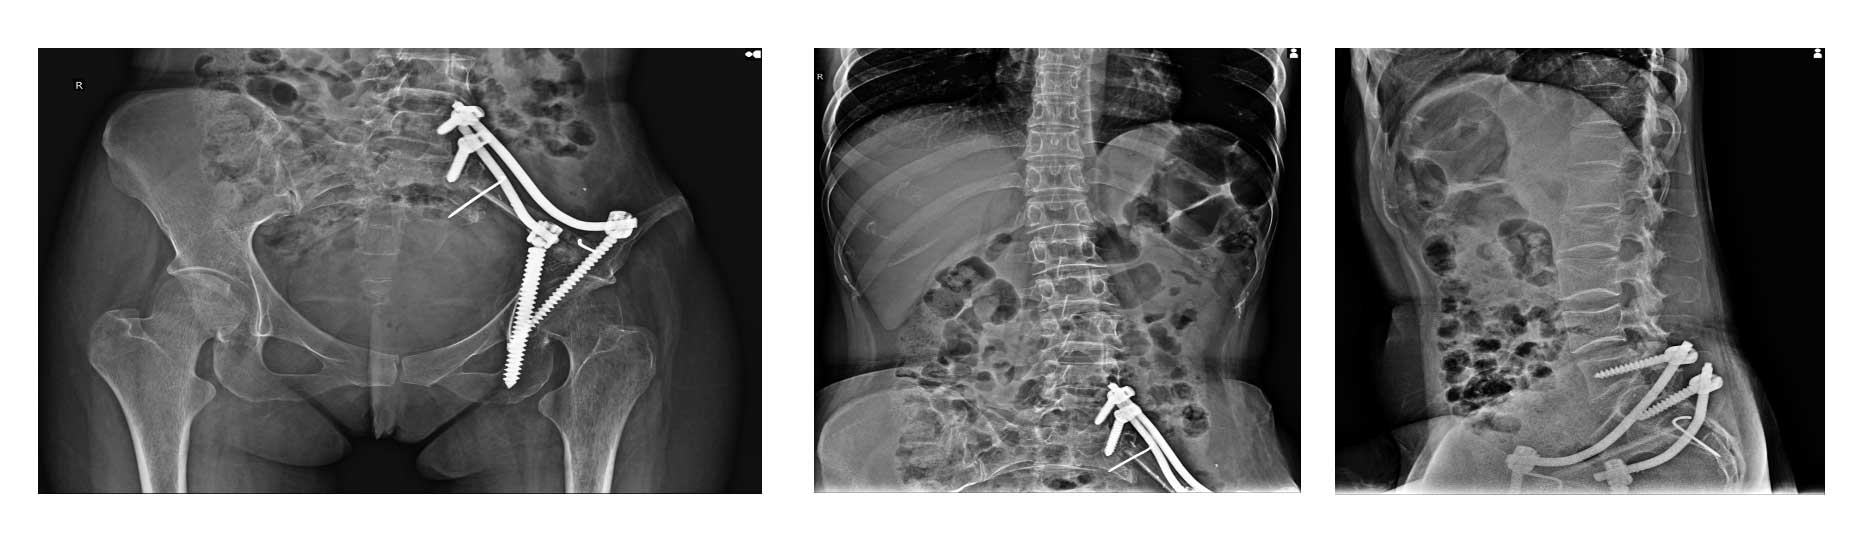

Ameliyat Öncesi: Röntgende ilk ameliyatta yapılan sakroiliak rezeksiyon ve rekonstrüksiyon, lomber vertebra kırıkları ve deformite görülmekte.